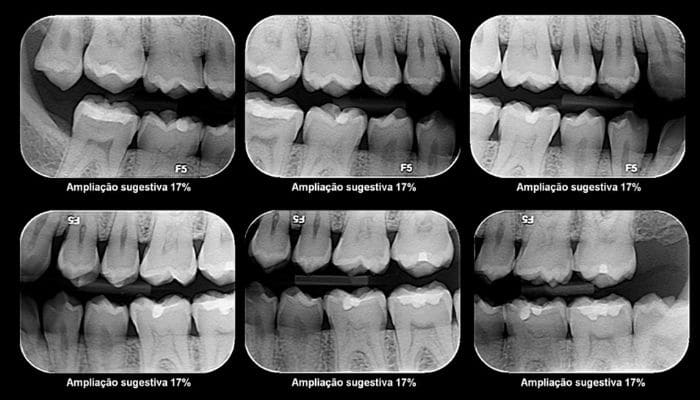

4. Radiografia interproximal – A radiografia interproximal é um exame que serve para visualizar as arcadas dentárias superior e inferior dos pacientes. A principal utilização desse exame é para pesquisar cáries nas faces interproximais.